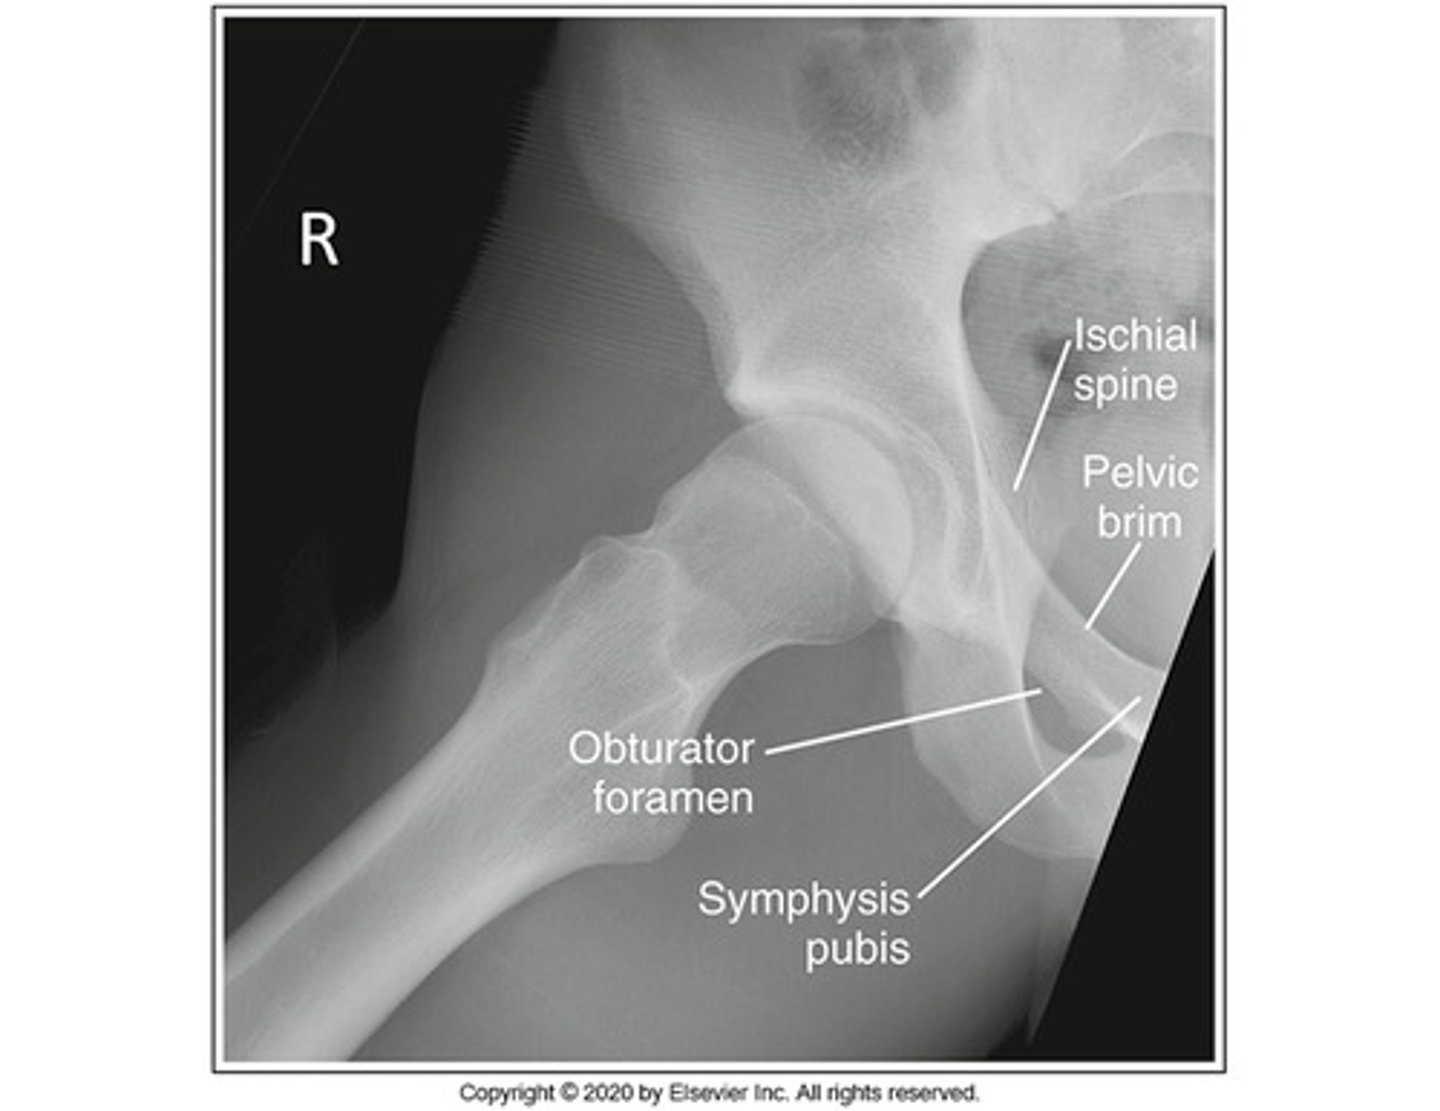

Which projection of the hip is shown in the figure above?

Axiolateral

The area of anatomy indicated on the figure above is the:

obturator foramen

Identify the projection:

AP hip

AP oblique hip

Lateral hip

Axiolateral hip